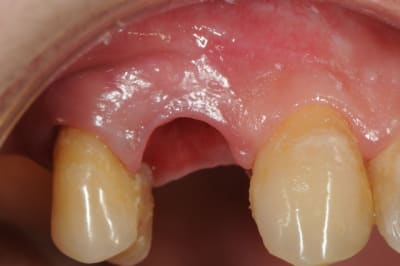

11 avec résorption interne

EII avec MCI sur du dentium (4.5/14) comblement du gap vestibulaire avec du kasios tcp (très constant dans les résultats...et très économique)

pas de photos de chir par contre...j'ai du les effacer par erreur...grrrr...

la prothèse d'usage a été réalisée par ma petite associée...mais j'étais là pour superviser et faire quelques photos...;-)

le biomat est du kasios tcp, on voit quelques granules qui s'éliminent de la gencive

une série de photo le jour de la pose, puis 15j après (prothèse réalisée par mon confrère)